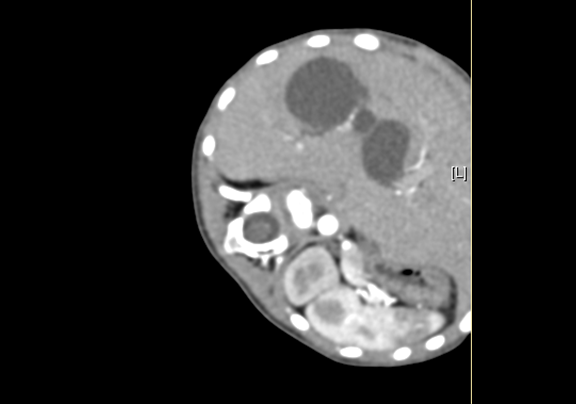

术前CT检查:

静脉期

上腹部增强CT:符合胆总管囊肿。

将0.625mm双源薄层CT资料的静脉期和动脉期Dicom格式文件导入海信CAS系统。

通过调节窗宽窗位调整CT序号,对肝实质,胆囊,胆总管,下腔静脉,肝动脉、门静脉及肝静脉等进行三维重建;系统自动计算肝脏体积。